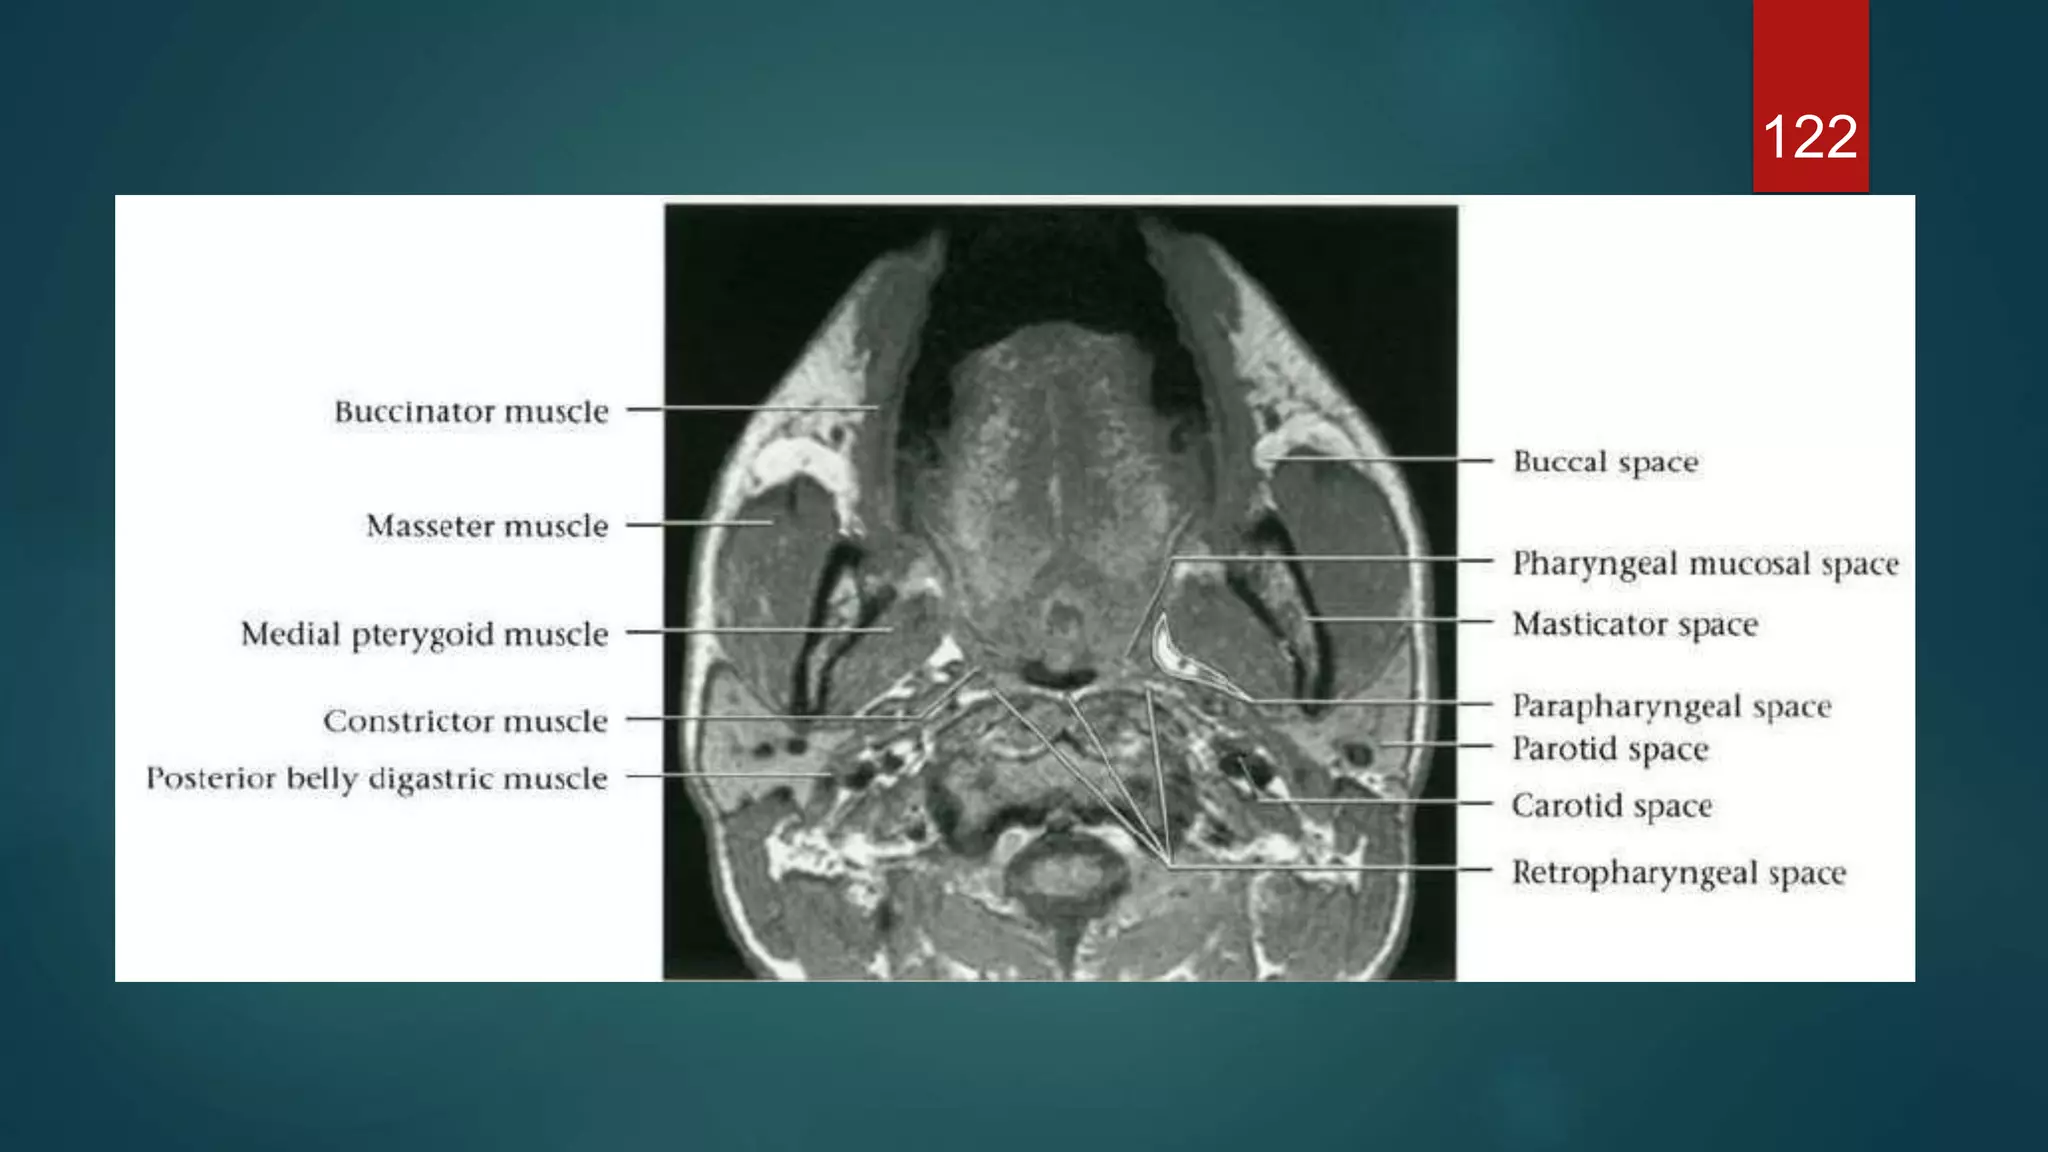

120

121

122